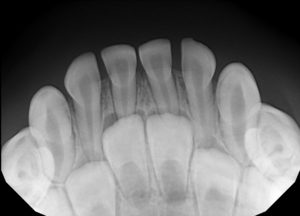

A visual exam is great for seeing the surfaces of the teeth, but a lot of dental health happens "under the hood." Digital X-rays allow us to see:

Definitely. One of the perks of our office is that we provide both pediatric dentistry and orthodontics. Dr. Beanca Chu and our orthodontist, Dr. Shawn Yu, use digital X-rays to track exactly how the permanent teeth are moving into place.

A panoramic X-ray (the one that rotates around the head) gives us a full "map" of the jaws. It helps us see if the jaw is aligned correctly or if there’s enough room for adult teeth to erupt. The American Association of Orthodontists recommends an evaluation by age 7, and having these X-rays on file allows us to catch bite issues early, often shortening the time your child might eventually need to spend in braces or clear aligners.